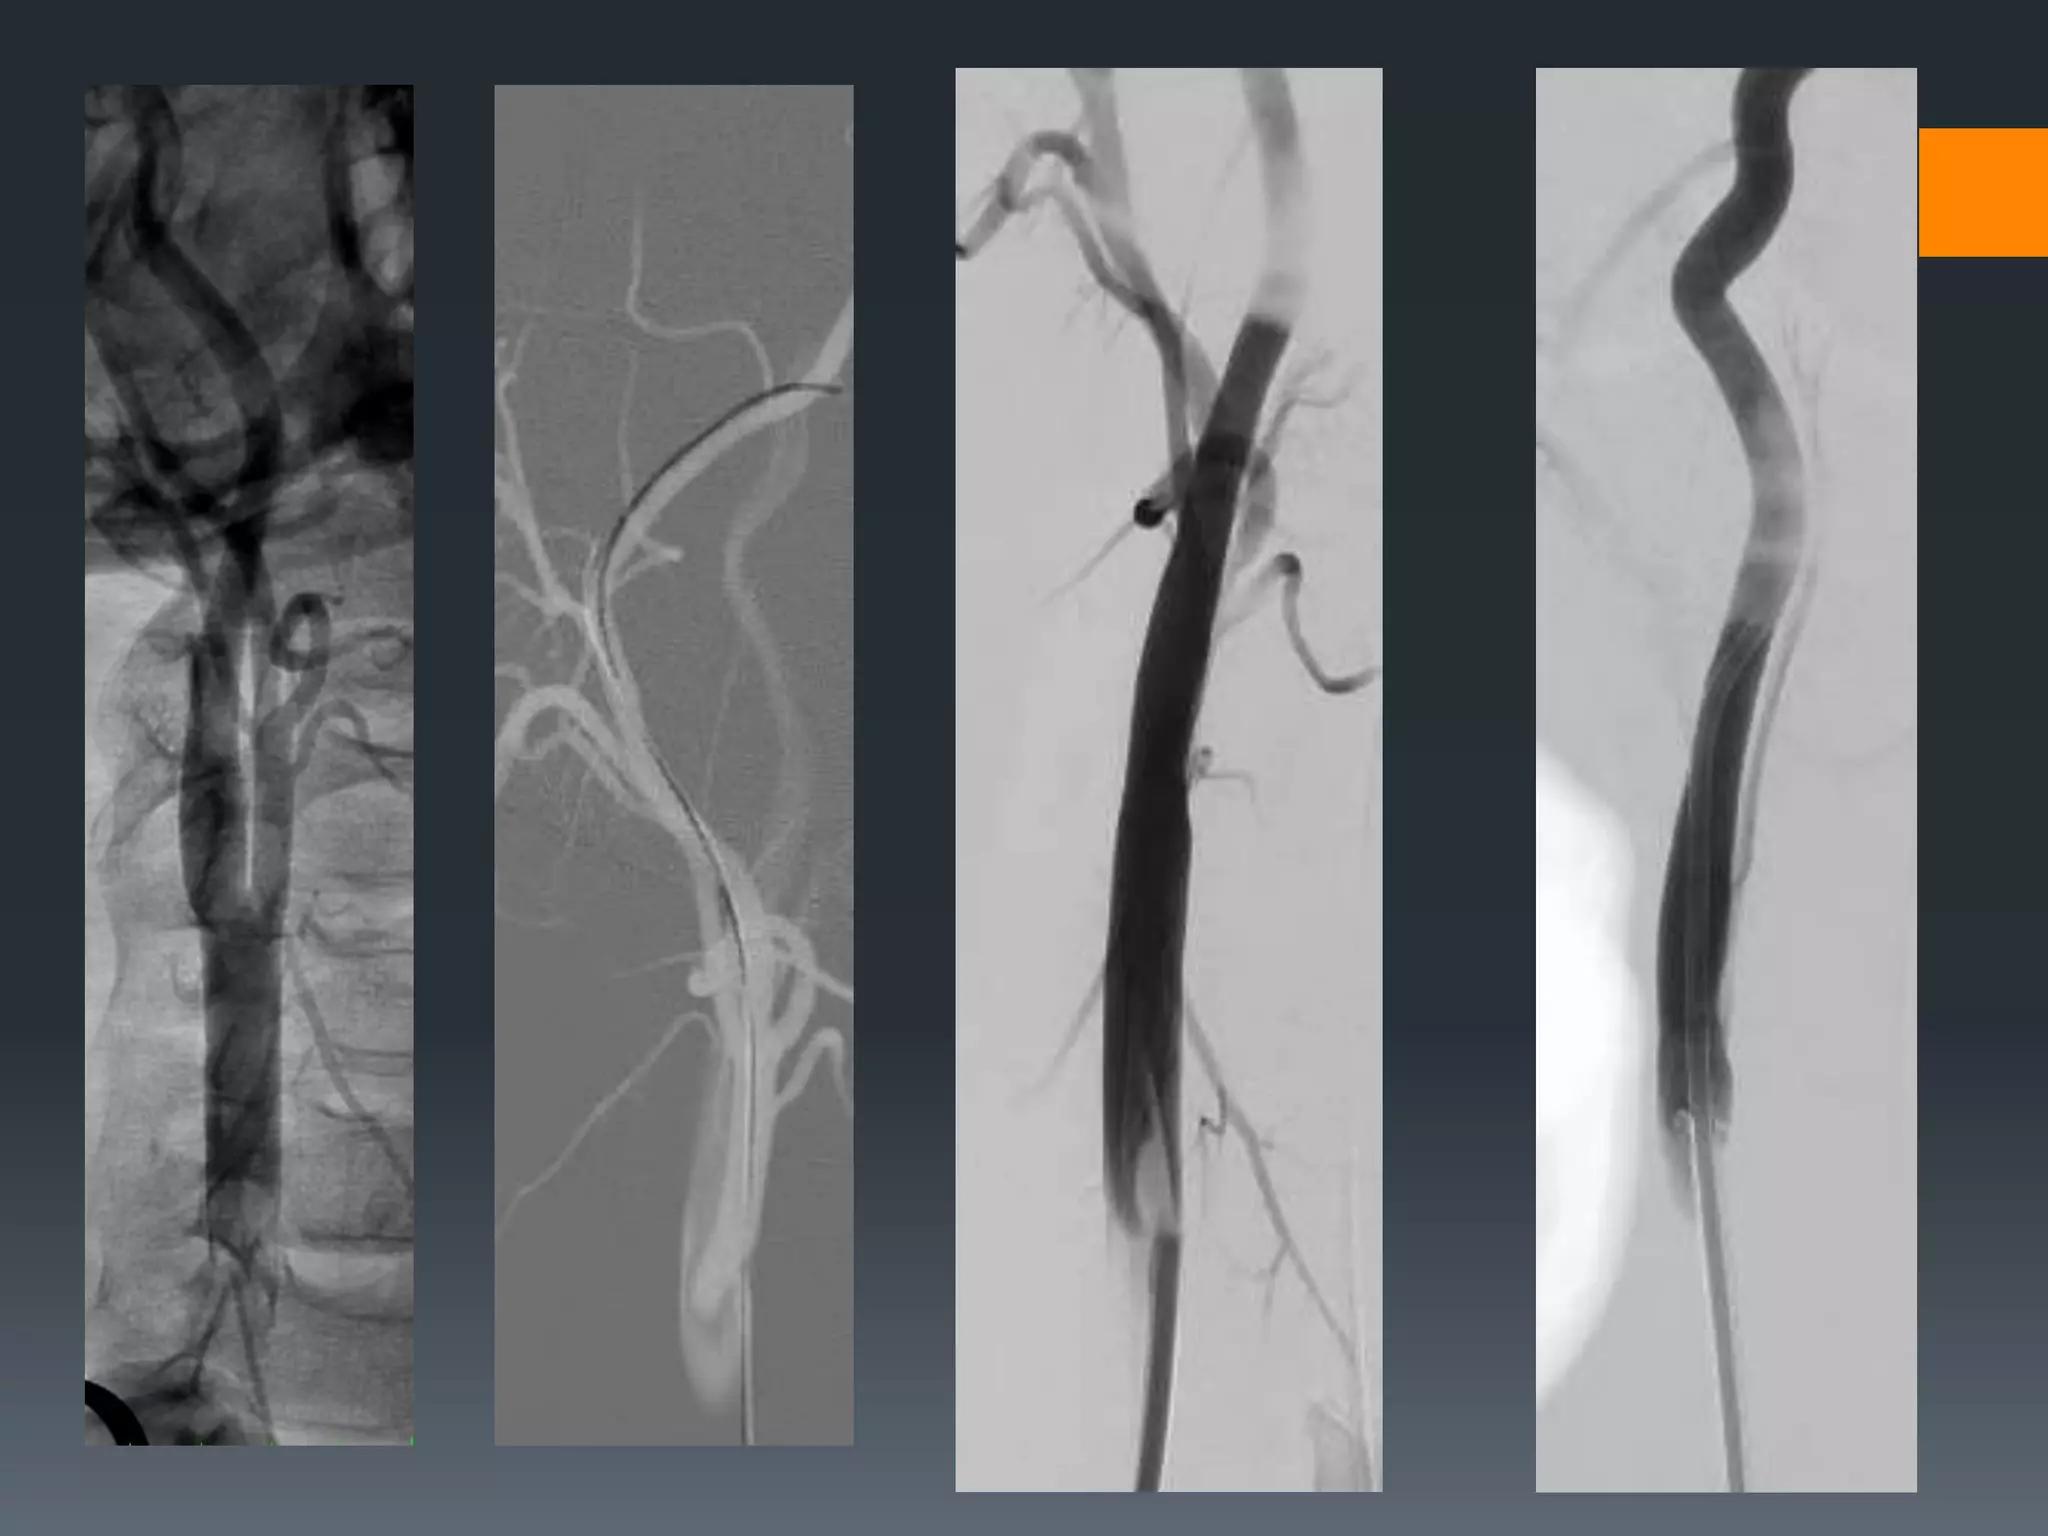

This document discusses tricks and techniques for difficult cannulations during neurointerventional procedures. It outlines strategies for accessing the aortic arch, internal carotid artery (ICA), and areas distal to aneurysms. Long sheaths, distal access catheters, and co-axial techniques are presented as options that have improved cannulation success. Guidance on sheath and catheter selection is provided for different vessel paths. The importance of catheter placement as high as possible in the ICA is emphasized. Reverse curve cannulations are also mentioned. Overall, the document stresses that careful cannulation is critical for procedural success and different strategies may be needed depending on the vessel target.